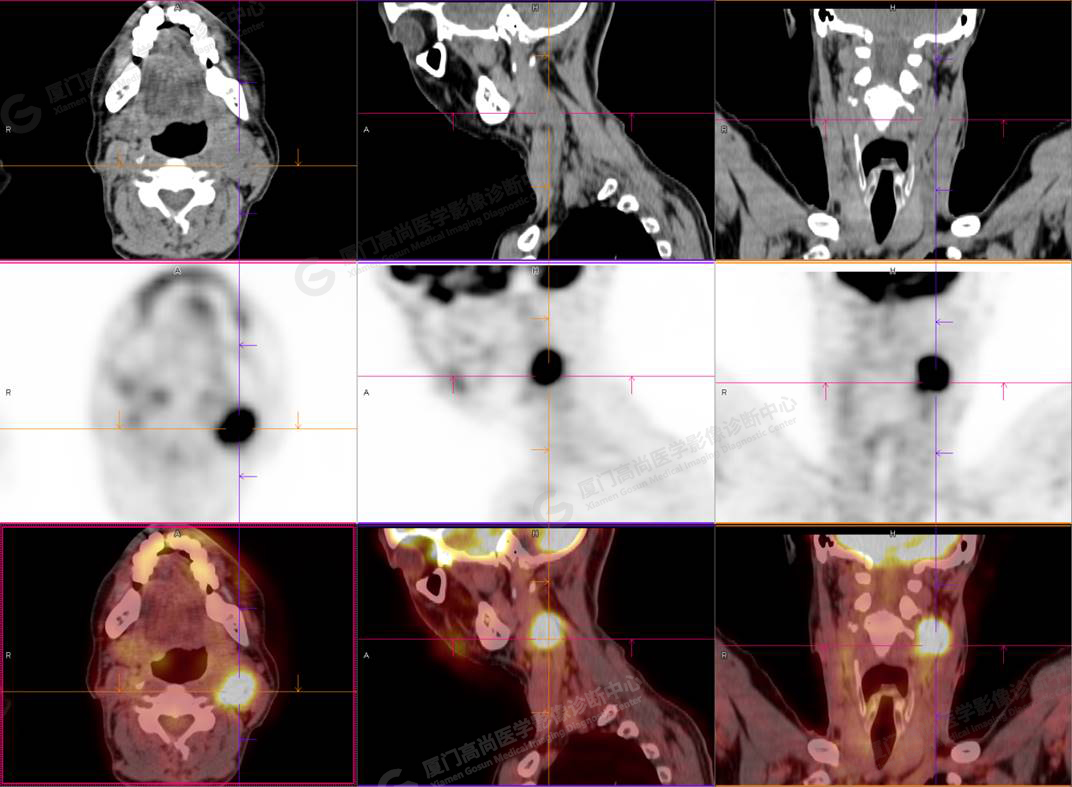

圖2

PET/CT所見:左側(cè)頸部(II區(qū))見腫大淋巴結(jié),大小約2.5cm×2.3cm,其內(nèi)密度不均,邊界尚清,放射性攝取異常增高,早期SUVmax 11.5,延時SUVmax 14.5。

影像診斷: 左側(cè)頸部(II區(qū))腫大淋巴結(jié),代謝異常增高,考慮腫瘤性病變可能性大(淋巴瘤?轉(zhuǎn)移瘤?),建議病理學(xué)檢查明確。

病理診斷:(左頸部結(jié)節(jié))副神經(jīng)節(jié)瘤。